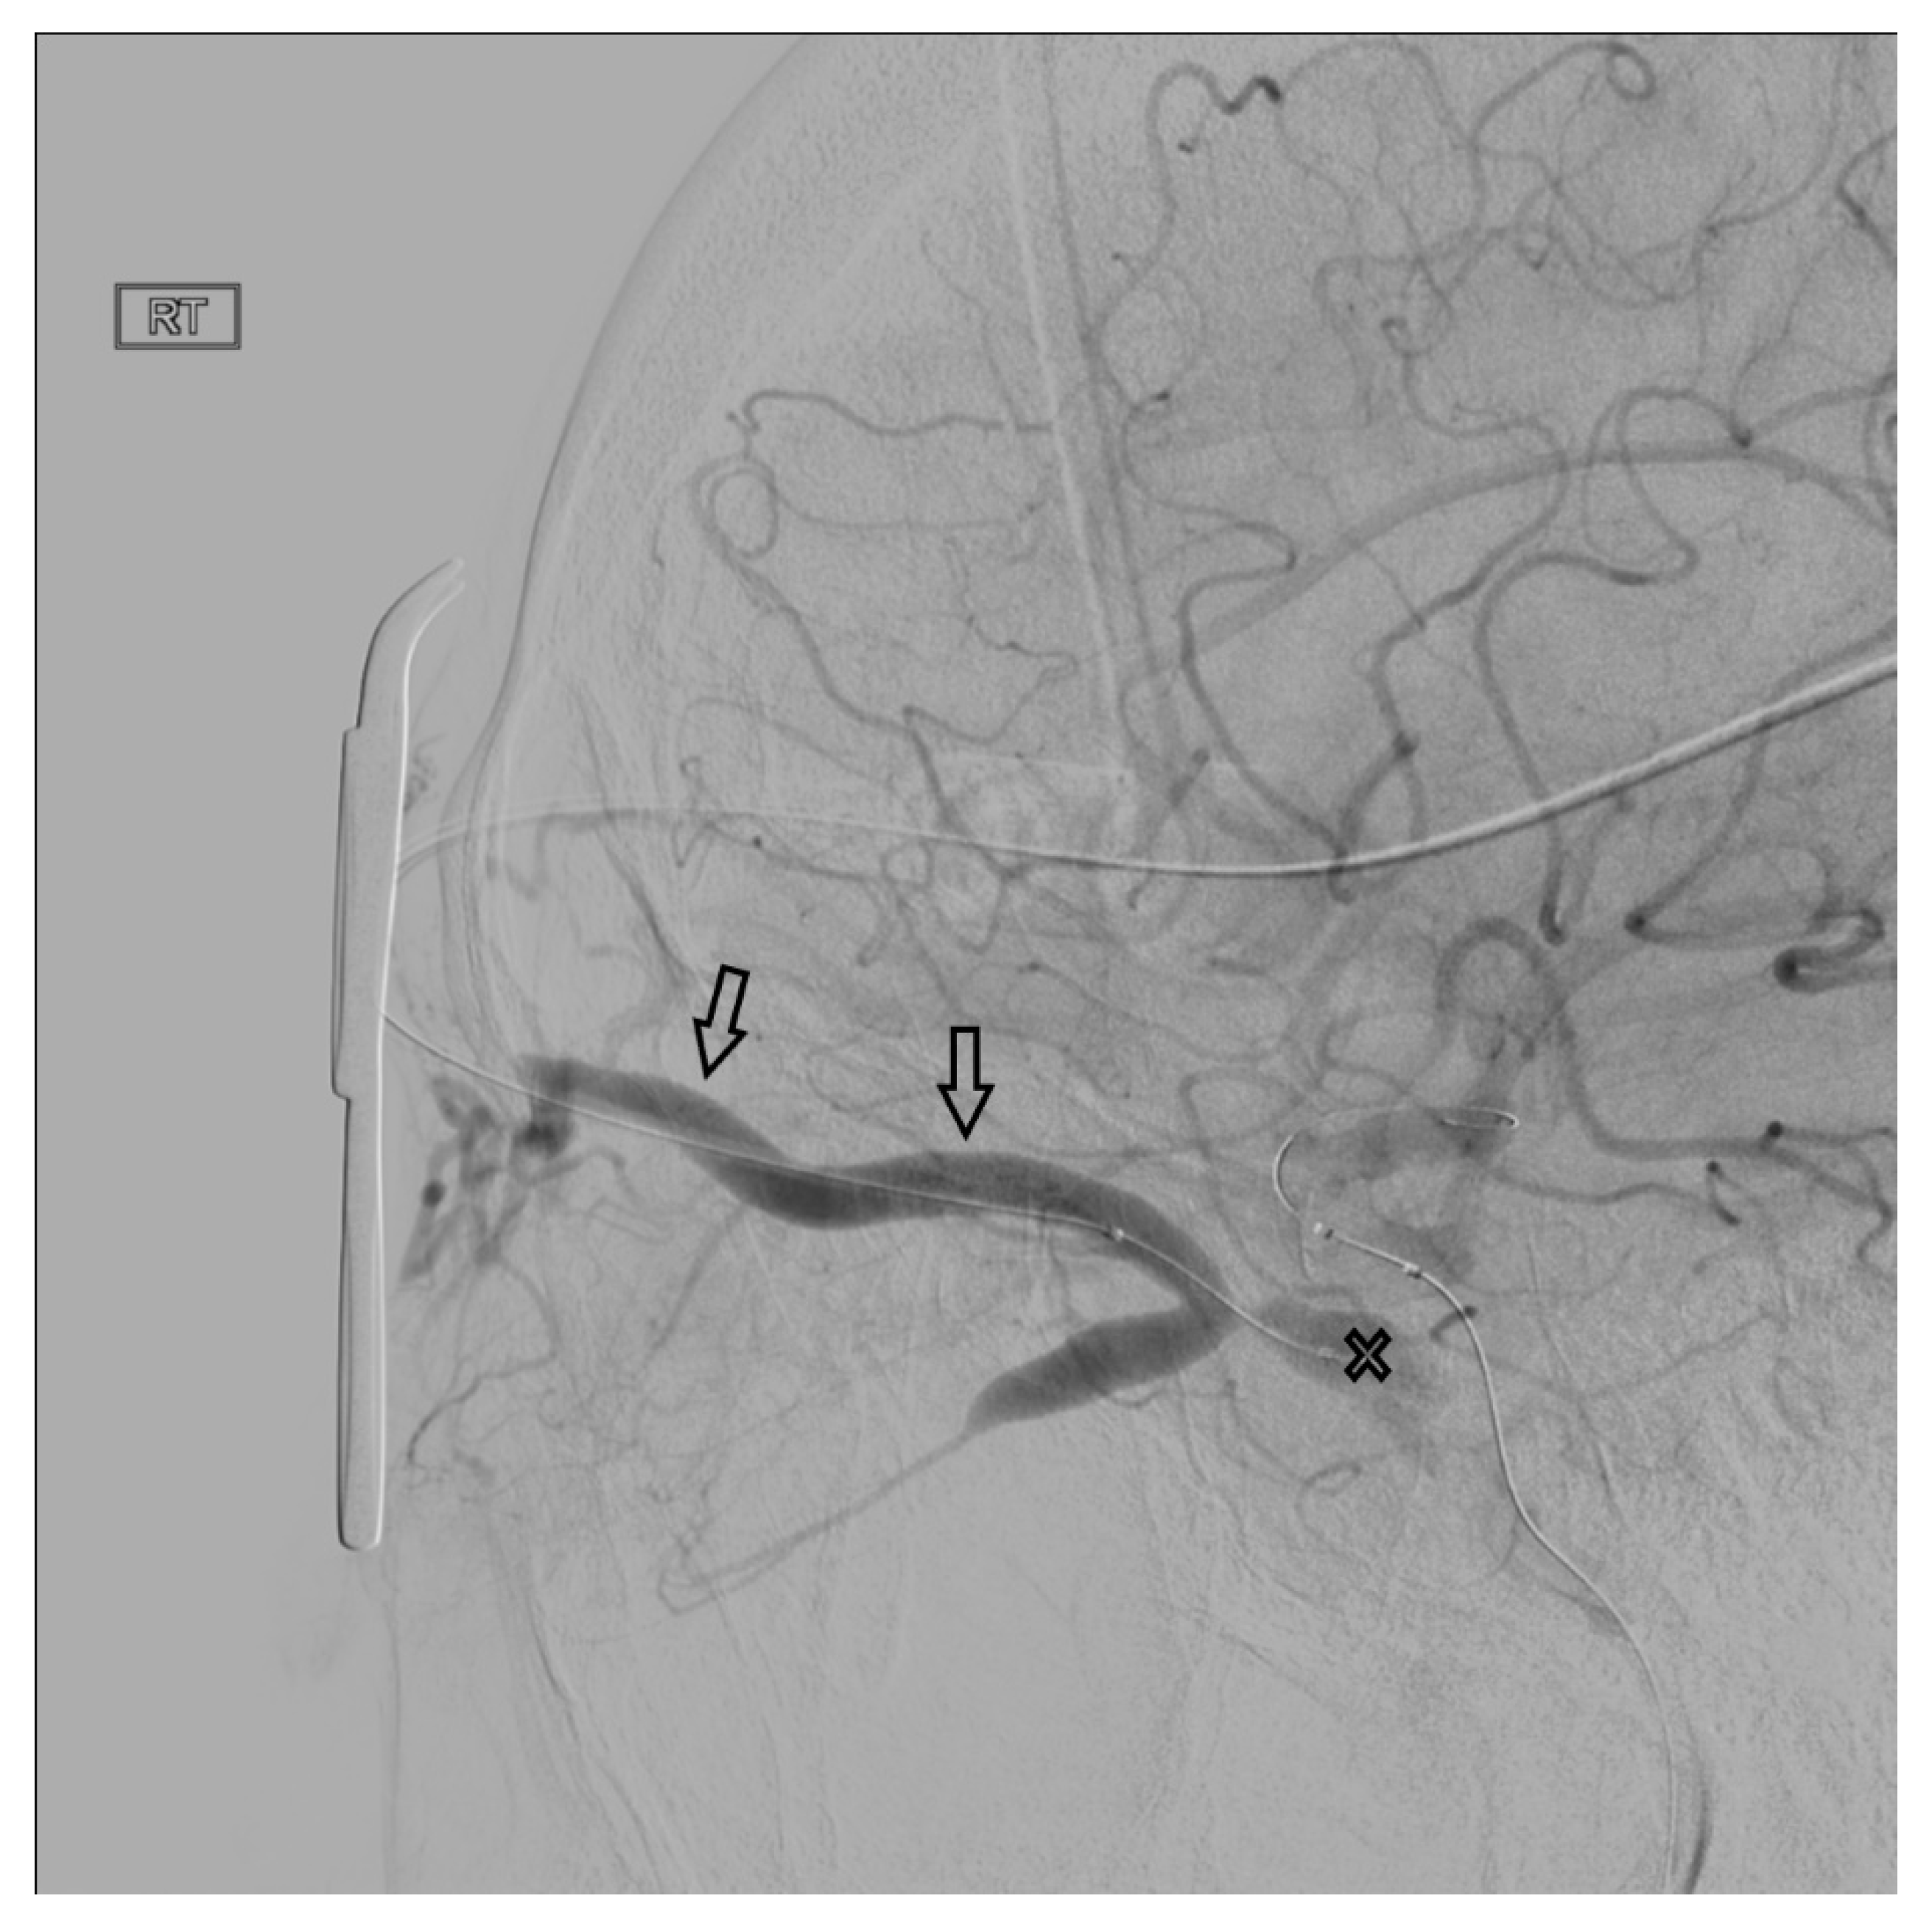

Figure 6. Demonstrates access of the left cavernous sinus (X) through an intercavernous approach (arrows).

In the setting of CCFs, the venous drainage may be primarily through contralateral pathways. Therefore, the best endovascular approach to a left sided CCF may be through the right IPS. Once the contralateral CS has been accessed, the ipsilateral CS can be accessed by crossing the intercavernous sinus, or more commonly through the clival plexus. The intercavernous connection is selected with a curved microwire directed either anteriorly or posteriorly. The microwire is then traversed across the intercavernous connection and, if necessary, looped within the opposite CS to provide support for the microcatheter to follow (Figure 6). This approach gives the operator the option of using virtually any of the described approaches on the contralateral side of the fistula site.